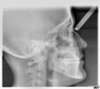

Téléradio Profil